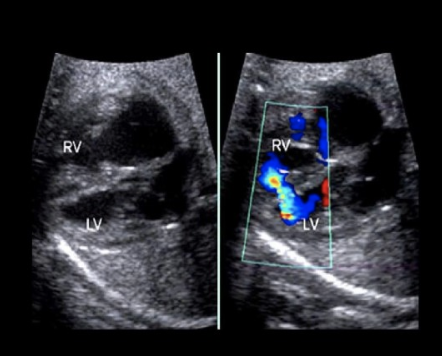

a) obtain a cross-section view of the umbilical cord insertion at the placenta + apply color doppler

b) obtain a transverse view of the fetal abd at the level of the kidneys + apply color doppler

c) obtain a transverse view of the fetal pelvis at the level of the bladder + apply color doppler

d) obtain a midline sagittal view of the fetus that includes the fetal bladder + apply color doppler